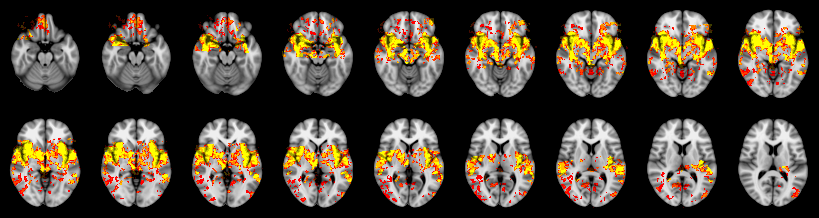

Pain study, TFCE, Uncorrected

Combined

Tippett:

Fisher:

Stouffer:

Edgington:

Mudholkar–George:

Friston:

IUT/Conjunction/Nichols:

Hotelling T2: